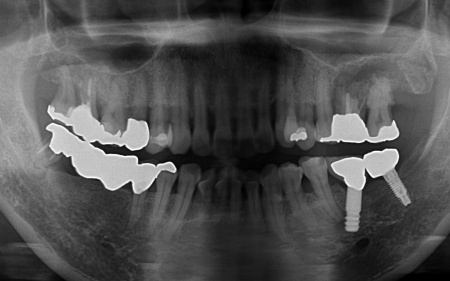

左上については、顎の骨が大きく失われているため、骨を再生させる処置「GBR(骨再生誘導法)」を実施してインプラントを支えるために必要な骨量を確保したうえで、インプラントを埋入する計画を立てました。

まずは左上奥歯2本を抜き、骨が足りない部分に骨補填剤を入れ骨の再生を促します。

経過観察後、十分な骨量を確保できたことを確認し、インプラントを埋入しました。

次に、右下に装着されているブリッジを除去してから右下の親知らずを抜き、欠損部(第1大臼歯、第2大臼歯の部分)にインプラントを埋入しました。

続いて、インプラントに装着する人工歯を作製します。

最後に、完成した人工歯をインプラントに取り付け、噛み合わせや見た目に問題がないことを確認し、治療を終了しました。